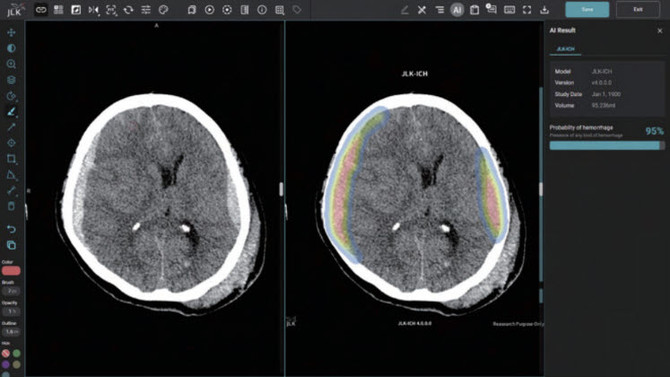

JLK-ICH는 제이엘케이가 주력하고 있는 뇌졸중 AI 솔루션으로 환자의 뇌 CT 영상을 분석해 뇌출혈 영역을 검출하는 AI 솔루션이다. 통상 뇌졸중 의심환자가 응급실에 도착하면 가장 먼저 뇌 CT를 촬영해 뇌출혈 여부를 확인하는데 이 과정에서 JLK-ICH가 빈번히 쓰일 것으로 예측된다.

JLK-ICH는 임상연구를 통해 발생 특징이 다른 5가지 뇌출혈 유형에 대해 편차 없는 높은 검출 성능을 입증한 만큼 골든타임 확보에 큰 역할을 할 것으로 기대된다.